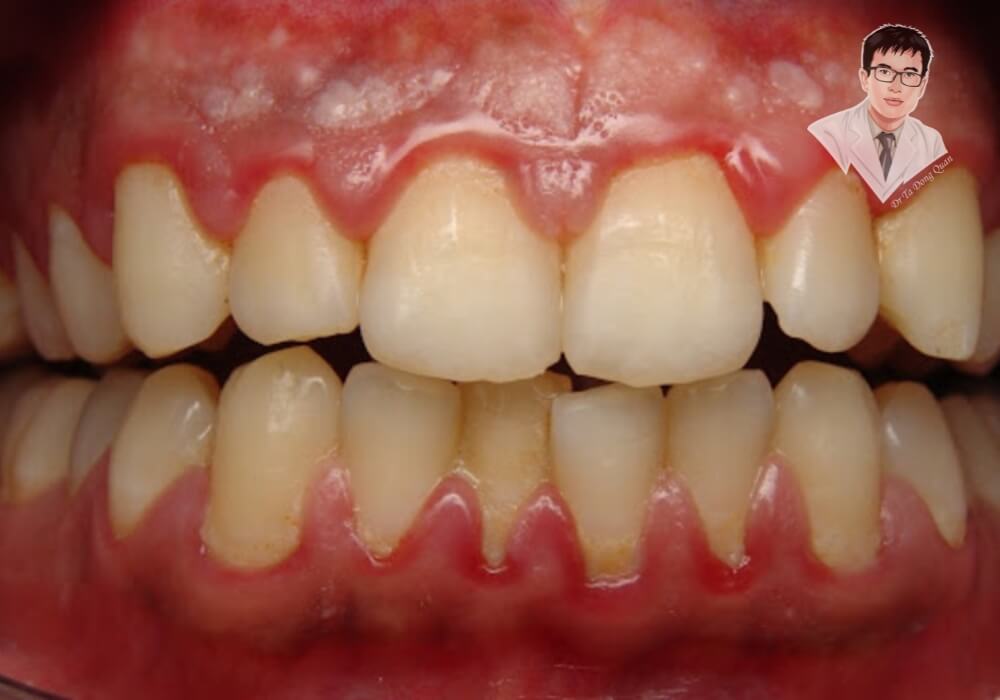

3. Chảy Máu Chân Răng Khi Đánh Răng

Nếu bạn thấy máu xuất hiện khi chải răng hoặc dùng chỉ nha khoa, đó có thể là dấu hiệu viêm nướu – một trong những nguyên nhân chính gây tụt nướu răng.

- Nướu chảy máu ngay cả khi đánh răng nhẹ nhàng.

- Chỉ nha khoa có dính máu sau khi sử dụng.

4. Nướu Sưng Đỏ, Đau Nhức

Tụt nướu răng không chỉ làm lộ chân răng mà còn khiến nướu dễ bị viêm nhiễm. Khi vi khuẩn tấn công, nướu có thể sưng đỏ, đau nhức và trở nên nhạy cảm hơn.

- Nướu có màu đỏ thẫm thay vì hồng nhạt.

- Xuất hiện cảm giác đau hoặc nhức nhẹ ở vùng nướu bị tụt.